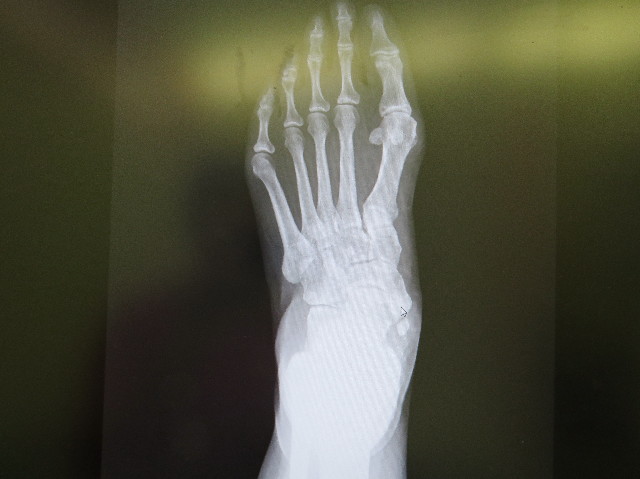

ママの左足を上から撮ったレントゲン

右側の指の付け根少し下(かかとの骨の上/内くるぶし)の、小さな白ポインターの位置が『外脛骨』です。(たぶん)

この『外脛骨』の出っ張りは日本人の場合、約15〜20%にしかない、余計な骨だそうです(85%の人はない)

で、『外脛骨』下に離れた骨がポツンとありますよね?

これはどうやら『外脛骨』の剥離?らしいです。(こりゃ痛そうだー(^^ゞ)

昨日今日ではなく、おそらくずっと前からこの状態だったけれど、捻挫や成人期扁平足や体重増加で急に痛くなったりするとのこと。